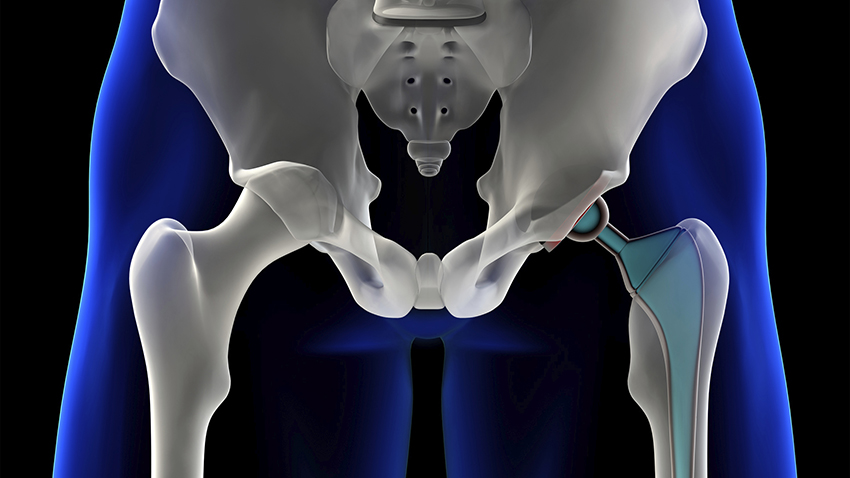

Hip replacement surgery is a procedure that is performed on patients who have a hip joint affected by arthritis. During hip replacement surgery, the surgeon removes the painful joint and replaces it with an artificial hip joint made from plastic, ceramic and/or metal.

Hip replacement surgery is a procedure that is performed on patients who have a hip joint affected by arthritis. During hip replacement surgery, the surgeon removes the painful joint and replaces it with an artificial hip joint made from plastic, ceramic and/or metal.

Total hip replacement surgery is done under general anesthetic. The procedure involves replacing the ball at the top of the femur (thigh bone) and the hip socket. The surgeon will either cement the artificial hip joint to the bone or use a part with a porous coating that the bone grows into. A new type of total hip replacement surgery is done through a small incision in the front of the hip, allowing for a faster recovery and less damage to the hip. However, it's important that the surgeon be highly skilled in this technique, or the results can be worse than with standard hip replacement surgery.

During hip replacement surgery, the surgeon removes the painful joint and replaces it with an artificial hip joint made from plastic, ceramic and/or metal.

The hip replacement procedure involves replacing the ball at the top of the femur (thigh bone) and the hip socket. The surgeon will either cement the artificial hip joint to the bone or use a part with a porous coating that the bone grows into.